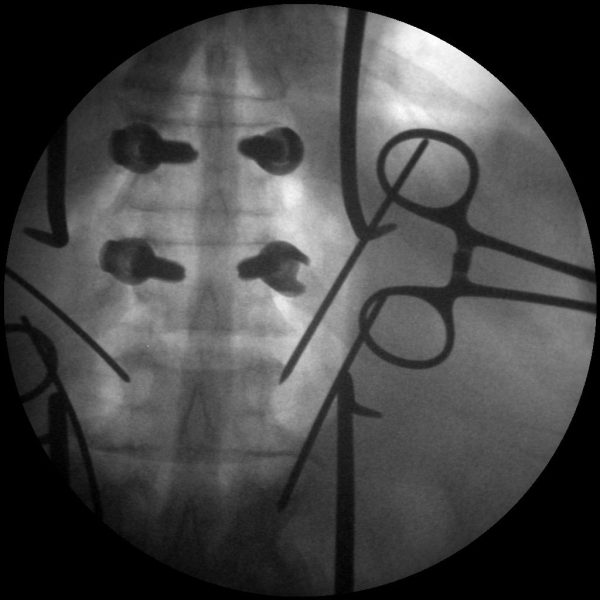

High-quality imaging

Skan-C uses advanced imaging technology, such as pulsed fluoroscopy and digital subtraction angiography, to provide highly detailed images of the affected area. This allows doctors to perform procedures with increased precision and accuracy, and better patient outcome

Clinical Evidence

Skan-C is a great C-arm for neurology treatments for several reasons